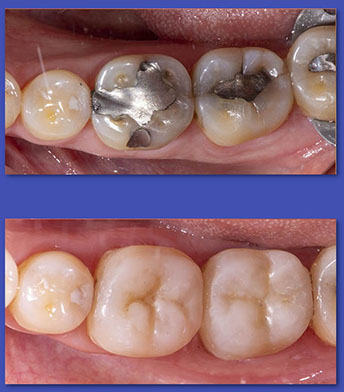

5. PRÓTESIS FIJA

(CORONAS Y PUENTES)

La prótesis Fija es el tratamiento indicado en aquellos casos en que la corona del diente está afectada completamente y se debe rehabilitar en forma íntegra, además en el caso de los puentes sirve para reponer de forma fija, dientes que fueron extraídos. La mayoría de las veces un diente con tratamiento de conducto requiere una corona para ser rehabilitado.

ANTES

DESPUÉS